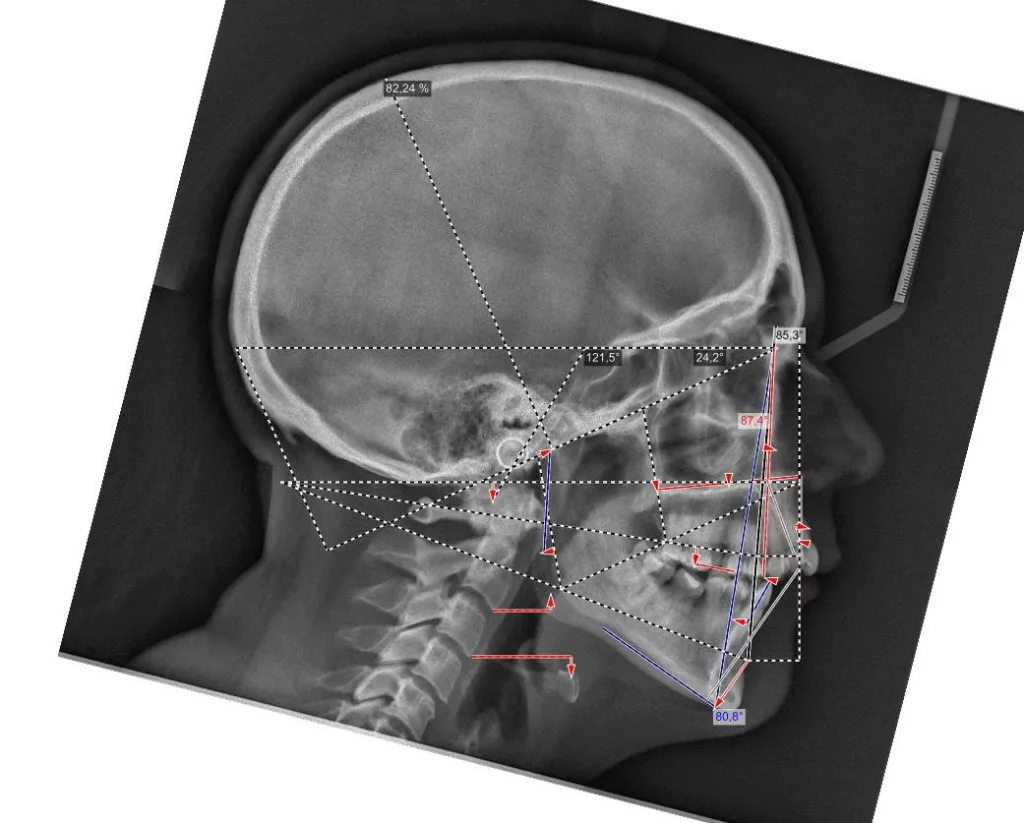

Parmi les examens radiographiques nécessaires, les radiographies de profil et de face correctement orientées et contenant l’ensemble de la tête (sommet du crâne inclus) sont particulièrement importantes. Ces radiographies correctement effectuées permettent d’établir une véritable cartographie du squelette du patient et en conséquence de comprendre sa malformation. Cette analyse cartographique du squelette a pour nom « céphalométrie ». De nombreux types d’analyses céphalométriques existent et sont utilisées selon les pays et universités. Parmi elles, l’analyse céphalométrique architecturale et structurale de Jean Delaire tient une place particulière.

L’Analyse Céphalométrique architecturale et structurale de Jean Delaire

L’analyse céphalométrique architecturale crânio-faciale de Jean Delaire, à la différence des autres méthodes d’analyse qui sont principalement basées sur des moyennes statistiques définissant ce qui est « normal » et ce qui est « anormal » (c’est à dire pathologique) est basée sur la notion d’équilibre ou de déséquilibre architectural du squelette crânio-facial propre à chaque individu en tenant compte des principaux appareils anatomiques à son contact et des principales fonctions qui interfèrent avec lui. « A l’état d’équilibre, tous les éléments de l’extrémité céphalique ; squelette et tissus mous sont et fonctionnent en parfait équilibre mutuel ».

Pour chaque individu, l’analyse architecturale crânio-faciale de Jean Delaire permet de déterminer « l’équilibre » squelettique idéal qui lui est propre c’est-à-dire « sa normalité » et de constater, s’il existe, l’état de «déséquilibre » dans lequel il se trouve, c’est-à-dire l’état « pathologique » dans lequel il se trouve en tenant compte de son âge, de ses antécédents personnels ou familiaux, de son état fonctionnel ou dysfonctionnel, de l’existence d’éventuelles pathologies associées.

Pour chaque patient étudié l’analyse céphalométrique de Jean Delaire permet de :

- Connaître et de quantifier le morphotype qui lui est propre

- Analyser la situation d’équilibre (la normalité) ou de déséquilibre (la situation pathologique) dans laquelle se trouve l’ensemble de son extrémité céphalique ; crâne, massif facial et rachis cervical (analyse architecturale),

- Déterminer la participation respective de chaque élément anatomique dans la malformation ; maxillaire, mandibule, os basal, os alvéolaire, dents (analyse orthognathique et dentaire),

- Evaluer l’anomalie de position de chacune des pièces et unités anatomiques et de connaitre la position qu’elles auraient dû avoir en l’absence de pathologie guidant ainsi au mieux le chirurgien dans son plan de traitement chirurgical (analyse topographique)

L’analyse architecturale est complétée par l’analyse structurale. Pour chaque patient elle consiste à examiner attentivement tous la « structure » de l’extrémité céphalique c’est dire l’anatomie de chacune des pièces squelettiques et des parties molles qui la compose pour mieux comprendre le mécanisme d’installation et d’entretien de la dysmorphose. En association avec l’analyse architecturale elle permet de poser le diagnostic le plus précis afin de choisir le meilleur traitement chirurgical et orthodontique.

Analyse céphalométrique d’une sujet orthofrontal, orthognathe, à l’état d’équilibre en Classe I squelettique et dentaire (Schéma original Jean Delaire)